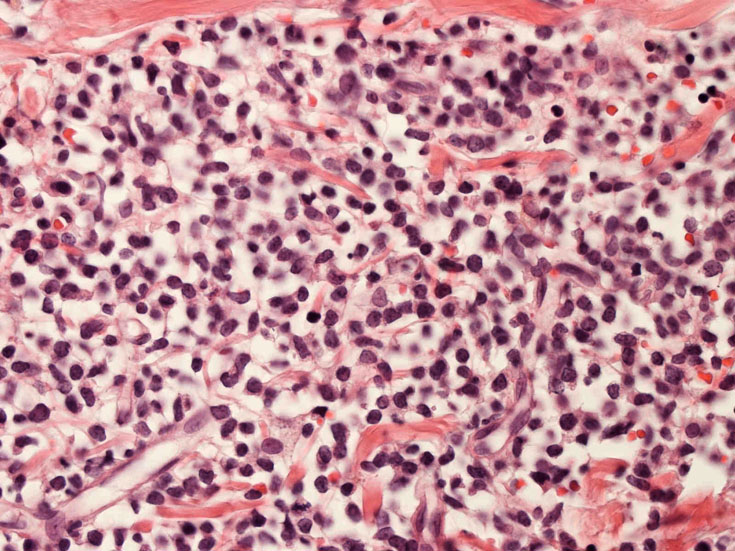

リンパ節病理組織所見

罹患リンパ節の基本構造は消失し腫瘍細胞のびまん性増殖で置換されている。非腫瘍性の小リンパ球(CD3+, CD4/8+)が濾胞様に散在して残る(Fig.01)。不整型または類円形の明るい核をもつmedium-sizeのリンパ球様細胞が密に増殖している。細胞質は乏しい(Fig.02)。CD68陽性macrophageが多く混在する部分が認められた。